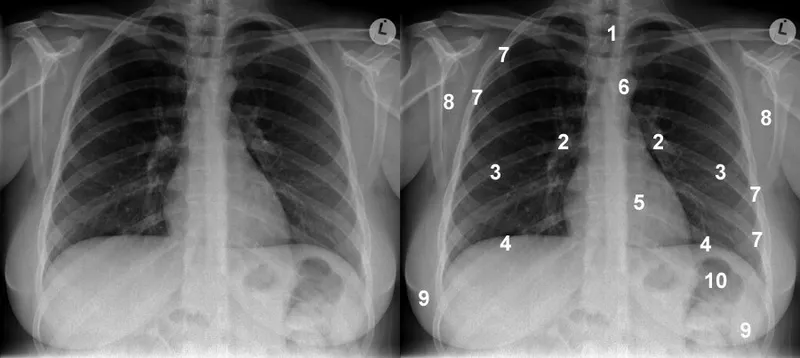

📌 Remember: ABCDEFGHI - Airway, Bones, Cardiac, Diaphragm, Effusion, Fields, Gastric, Hila, Implants - Systematic chest X-ray evaluation sequence

💡 Master This: The silhouette sign principle - loss of normal anatomical borders occurs only when pathology is anatomically contiguous with the structure, enabling precise lobar localization of pulmonary disease